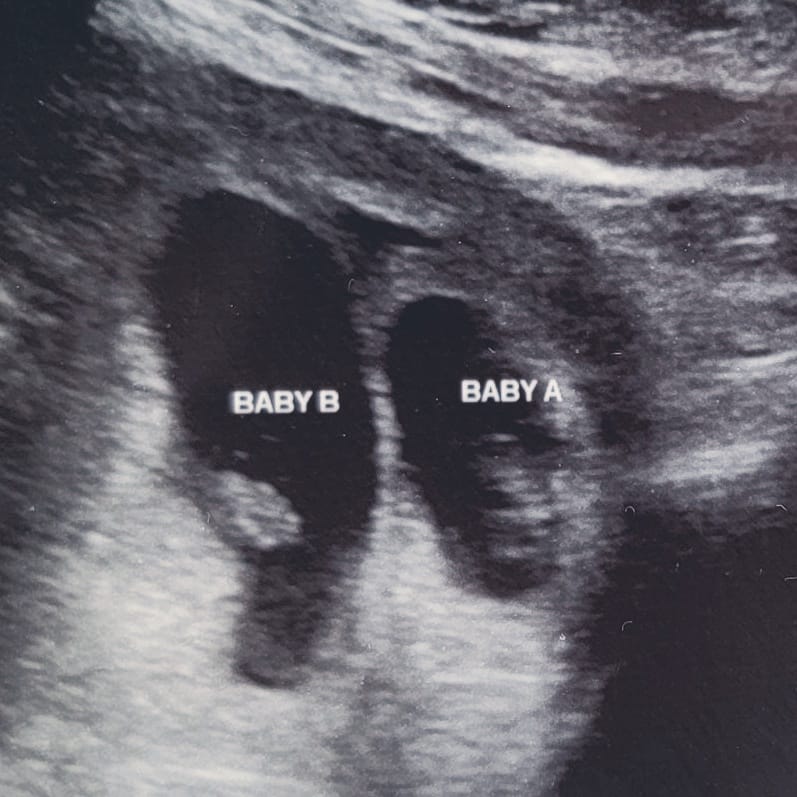

I went to Pregnancy Services for an ultrasound, still waiting on my Medicaid to come through. My mom came with me, running a little behind (as always). The tech turned the screen toward me with a spark in her eye, “there are two.”

Twins. 💫

We heard my mom’s footsteps in the hall, and the tech whispered, grinning, “Let’s see if she notices.” She did—immediately. For a heartbeat, the universe felt bewitched, like I was carrying not just life, but a spell doubled back on itself.

But December brought shadows. Spotting again. The dread that history was repeating itself.

The OB explained Vanishing Twin Syndrome (VTS)—a condition in which one twin is lost early in pregnancy, reabsorbed into the mother’s body or pressed into the surviving sibling’s growth. It happens in up to 30% of twin pregnancies.

Common, yes. Easier, no.

One heartbeat silenced. One heartbeat still steady, flickering like a candle flame on a stormy night. 💓